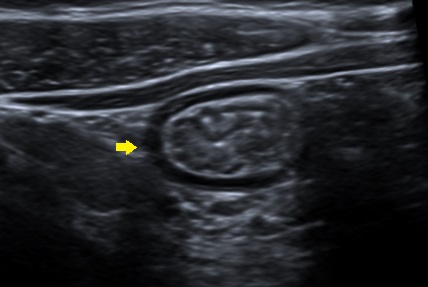

Niño de nueve años con antecedente de alergia a frutos secos, fruta y tomate natural, en seguimiento por Alergología. Consulta por dolor abdominal y deposiciones en número de 3-4 al día, de consistencia blanda, con sangre entremezclada, de dos meses de evolución. Niega ingesta de fármacos. No presenta astenia, pérdida de peso ni fiebre. En el estudio inicial destacan una eosinofilia periférica de 800/mm3 y una calprotectina fecal de 1230 mg/kg. En el estudio de heces no se observan parásitos, bacterias o virus y la toxina de C. difficcile es negativa. Se repite calprotectina fecal al mes, con nuevo valor de 1930 mg/kg y analítica con eosinofilia de 800/mm3. Se decide colonoscopia, que macroscópicamente es normal, pero el estudio anatomopatológico es compatible con colitis eosinofílica (Fig. 2). Se inicia tratamiento con budesonida oral, con mejoría clínica.

| Figura 2. Mucosa colorrectal. Izquierda: leve distorsión arquitectural e incremento de la densidad celular en la lámina propia a expensas de un infiltrado inflamatorio crónico con predominio de eosinófilos (ver indicador). Derecha: a mayor aumento se observan células binucleadas con gránulos específicos citoplasmáticos que se tiñen de rojo brillante con eosina (flechas). Se contabilizan hasta 63 eosinófilos por campo de gran aumento |